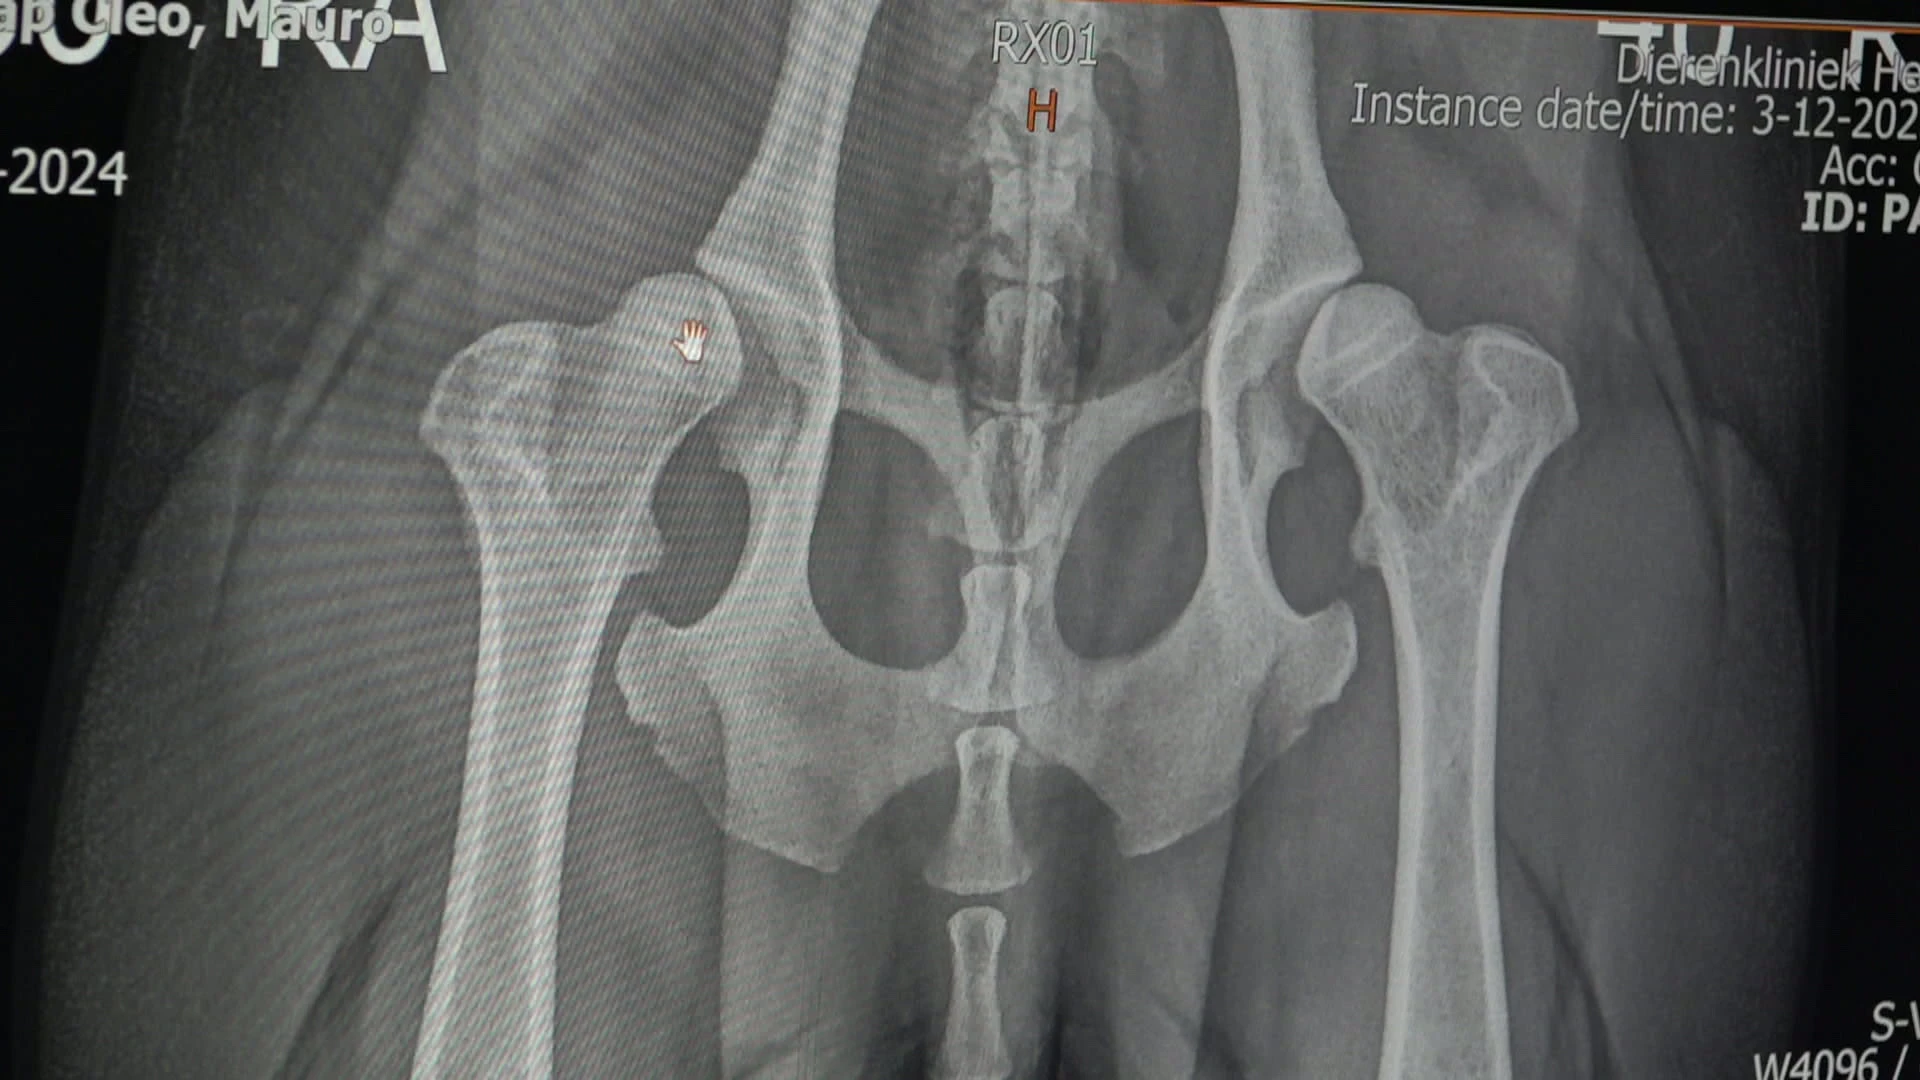

In Anicura Dierenartsencentrum Herckenrode in Hasselt zijn er twee op maat gemaakte 3D-geprinte titanium heupimplantaten geplaatst bij een beagle. Hij kampte al een tijd met pijn bij het rechtkomen en het maken van lange wandelingen. De techniek is nog maar sinds kort beschikbaar in België.